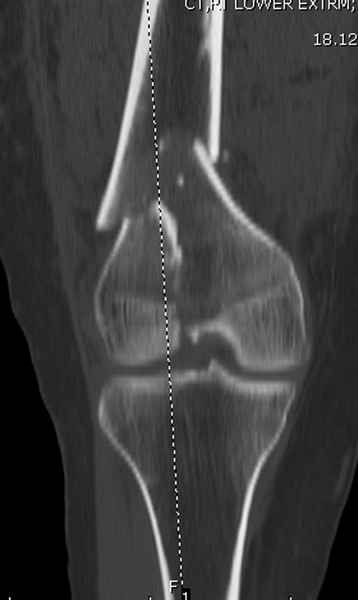

Приветствую всех коллег!!Во первых слева хотелось бы видеть четкую боковую проекцию а лучше КТ. По р-мам есть сомнения насчет повреждения суставной поверхности. При подобных переломах даже внутрисуставных без смещения хорошие результаты показал закрытый ретроградный остеосинтез универсальным бедренным стержнем Деост.Кстати при внутрисуставном переломе возможно применение вместо винтов стягивающих болтов!!(См. метод.Деост).При переломе справа также стержень Деост. Однако без открытия Вам не удастся устранить интерпозицию, только промучаетесь!Из минимального разреза удалите интерпозициб и фиксируйте стержнем. Причем универсальный стежень Деост позволяет фиксировать дистально минимум на трех уровнях!